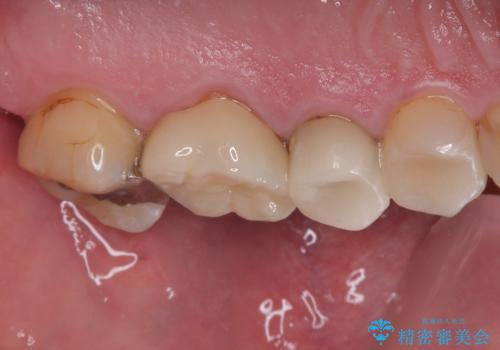

- 銀歯が取れたとのことで来院された患者様です。患者様の歯をあまり削りたくないというご希望に添い、セラミックインレーにて治療を行うこととなりました。

拡大鏡視野下で、保険のプラスチック、虫歯の除去を行い、セラミックインレーに適した形に整えました。